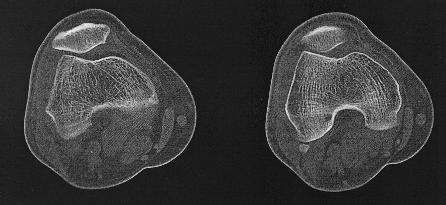

Ct knie 3D reconstructieCT Knie

Een Ct-scan van het skelet wordt uitgevoerd wanner er een verdere evaluatie nodigs van een lestel dat gezien is op een klasieke foto. Denk aan fracturen, luxaties e.d., maar ook aan metastasen, arthrose,...Zo kan het bijvoorbeeld zijn dat een letsle niet duidelijk genoeg voorkomt op de foto's endat er dus twijfel bestaat. Maar ook kan het zijn dat een CT-scan noodzaklijk is om een duidelijk beeld te verkrijgen van een uitgebreide fractuur, om verder behandeling te bepalen.

Dankzij de moderne computertechnieken is het niet allen mogelijk om axiale beelden te maken. (lees schijfjes dwars op het lichaam) Maar ook om die beelden te reconstrueren tot een 3D-model. Dit geeft vaak een duidelijk beeld van het bot, en zijn letsel.